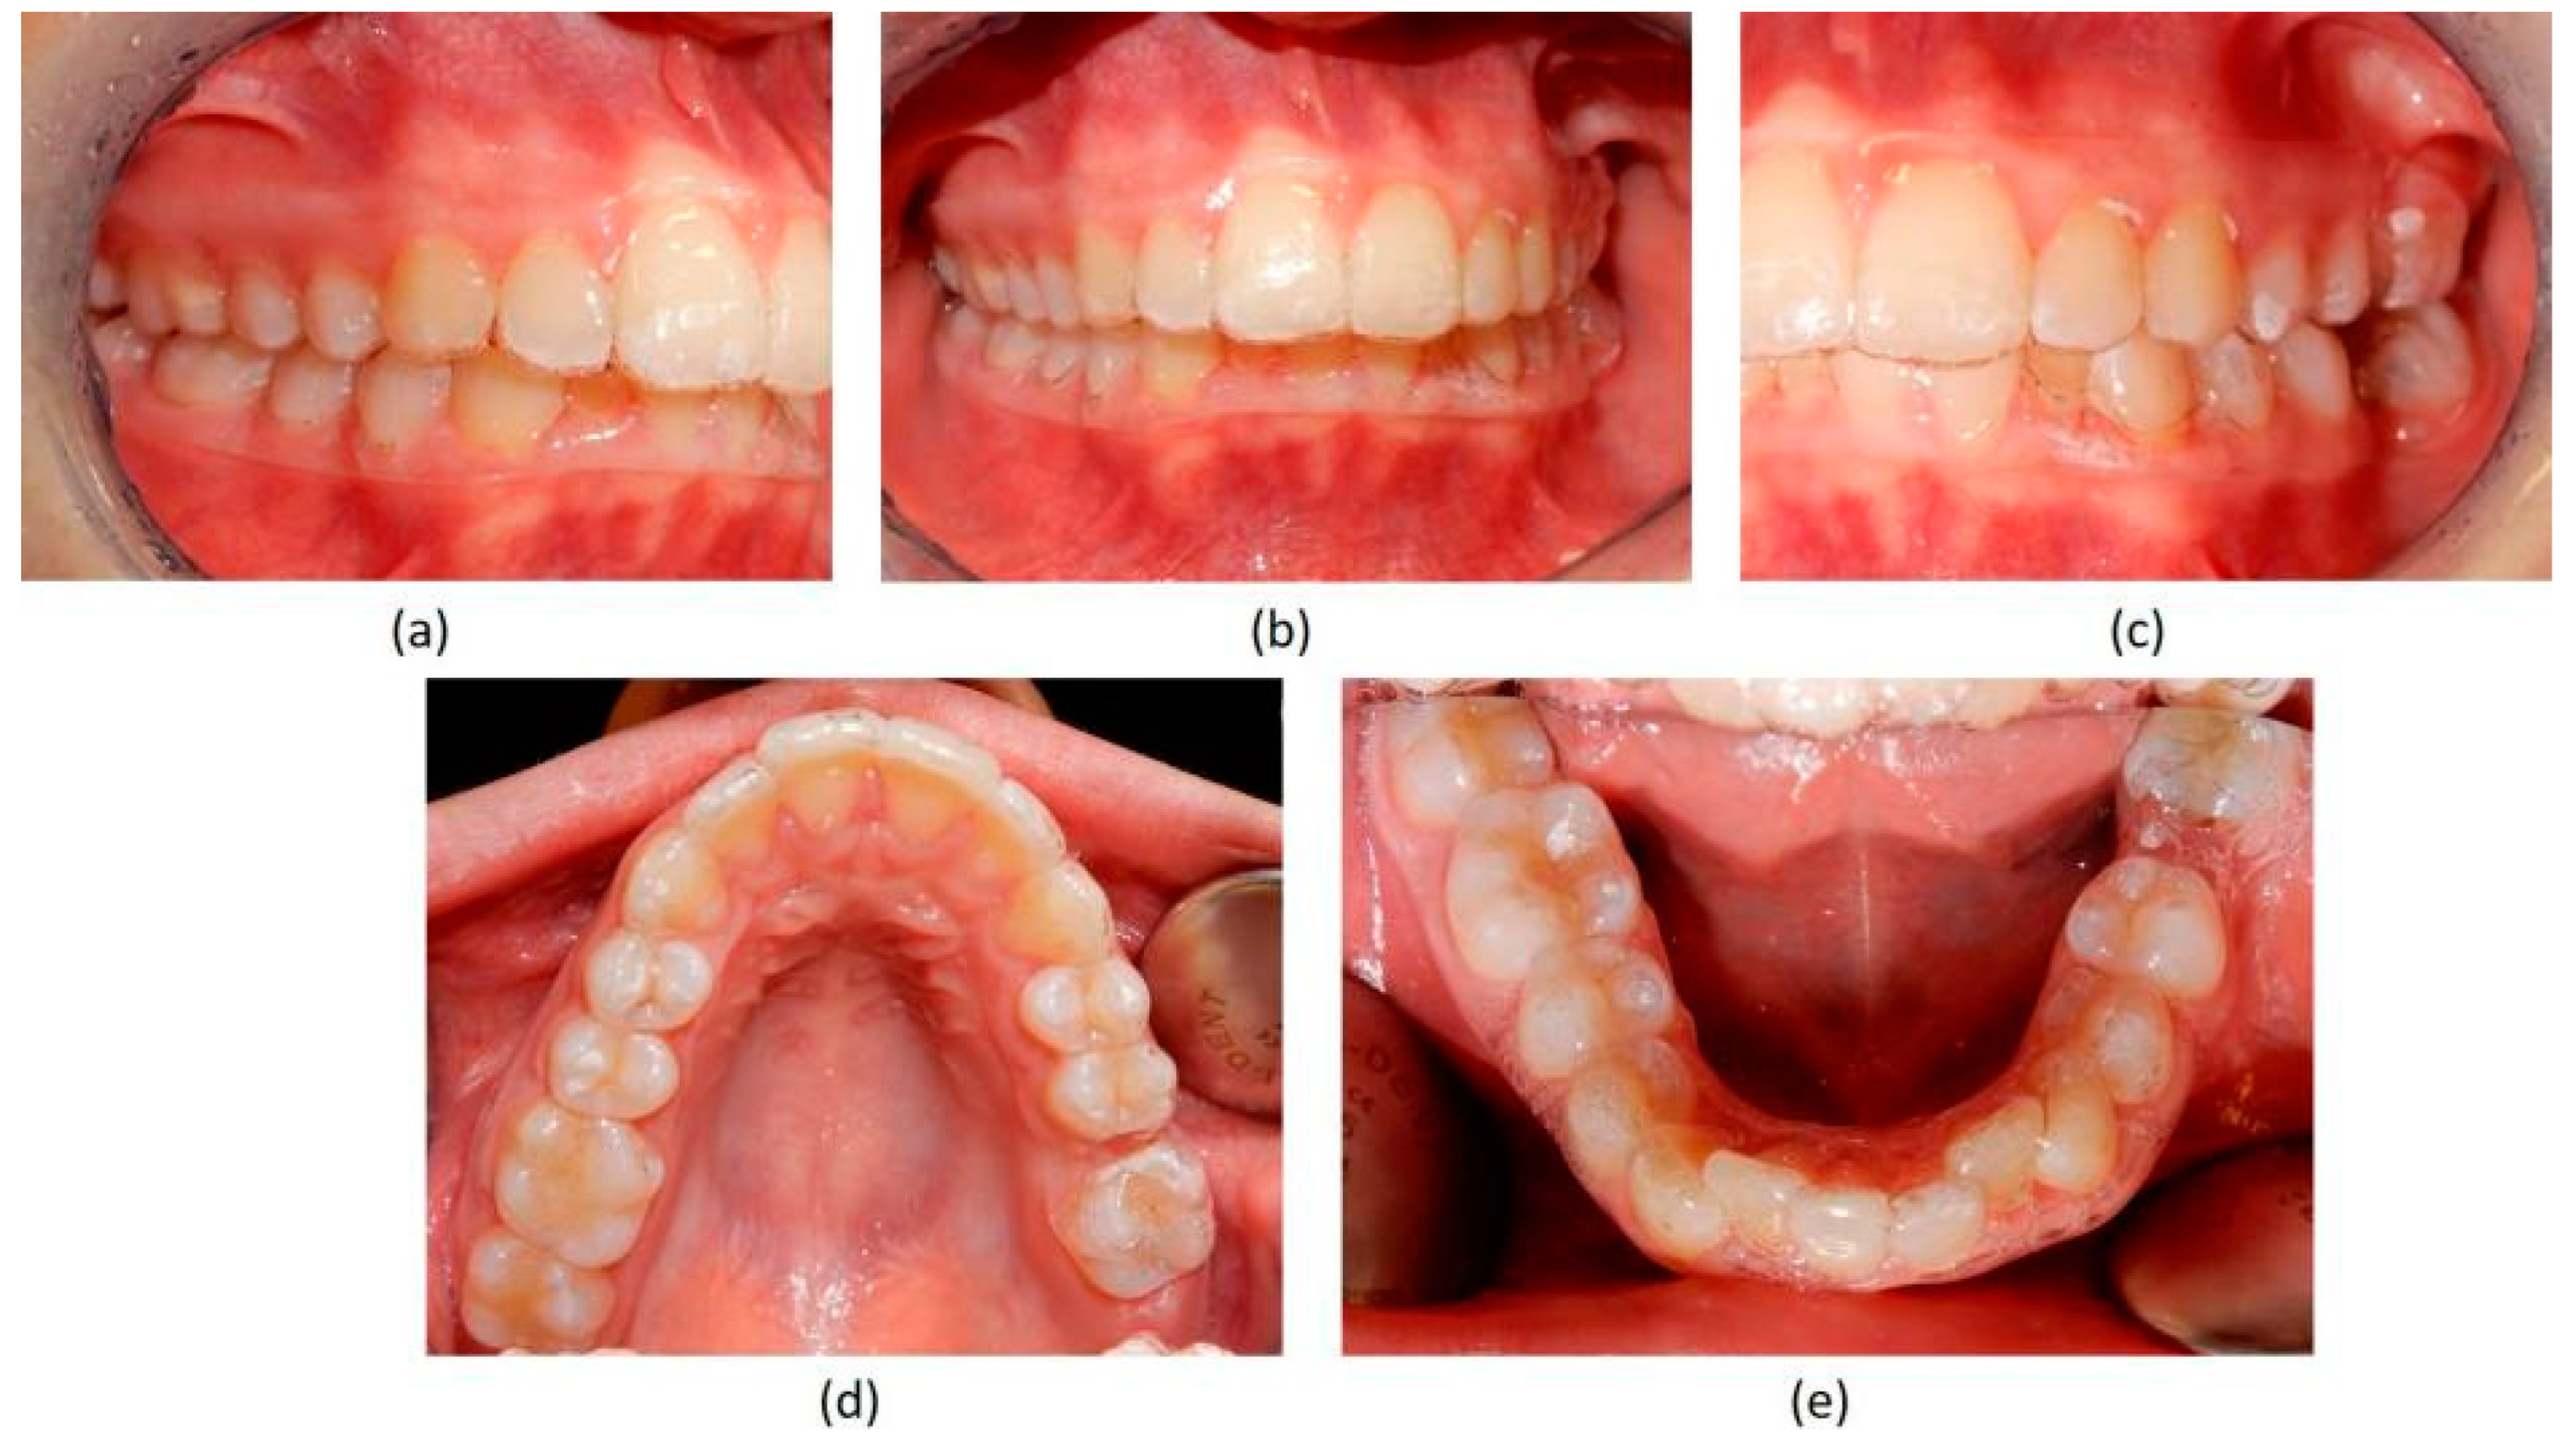

Figure 3.

Pre-treatment intraoral photographs. (a) right-side view; (b) deep bite in frontal view; (c) absence of the two first molars on the left side; (d) upper occlusal view showing the absence of the left first molar; (e) lower occlusal view showing the absence of the left first molar and the moderate crowding of the incisors.